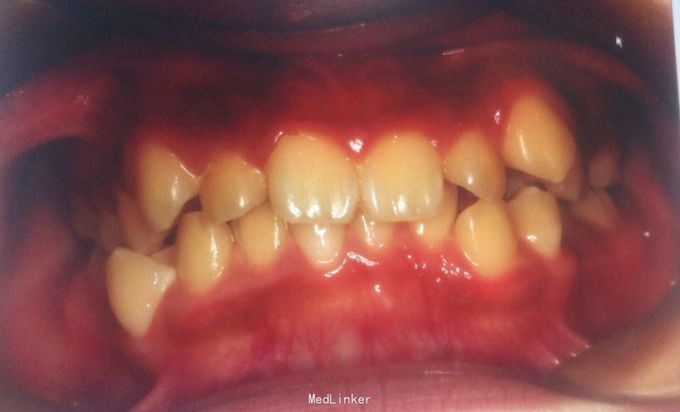

牙齿不齐、安氏一类

主诉:牙齿不齐 发现牙齿畸形,未曾正畸治疗,否认家族遗传史

恒牙期 33,44唇侧错位 磨牙中性关系 前牙覆合2度、覆盖1度 牙列拥挤

牙列拥挤、安氏一类 拔牙矫治,拔除14、24、34、44(强支抗)排齐整平上下牙列,直丝弓矫治器,关闭拔牙间隙,矫治后前牙覆合覆盖正常,磨牙中性关系,面型略改善